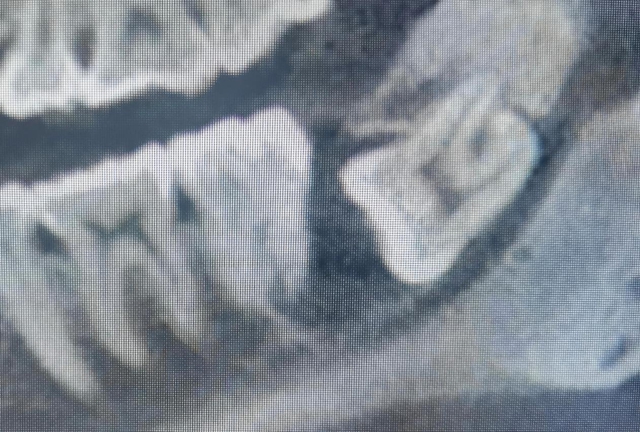

随后小伙做了口腔颌面锥形束 CT(口腔CBCT)检查,真相才水落石出:这是一颗水平低位阻生智齿,整颗牙横着埋在牙龈里,完全没法正常长出来。

不仅如此,牙冠周围的组织还一直分泌液体,慢慢形成了包裹着牙冠的含牙囊肿,囊肿已经波及旁边牙齿的牙根,还挨着下颌神经管,要是贸然拔牙,很容易伤到邻牙和神经管。